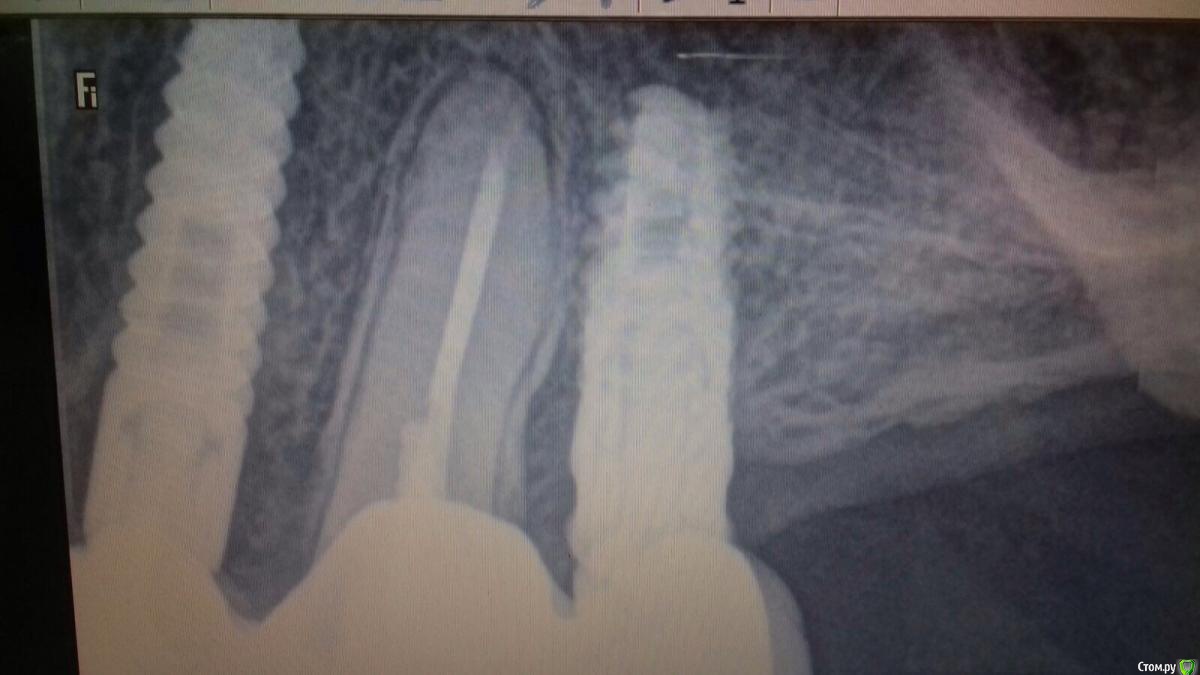

Rusty Опубликовано 13 ноября, 2015 Поделиться Опубликовано 13 ноября, 2015 Добрый вечер. Коллеги подскажите что за винт. На снимке медиальнее который. Абатмент временный Ссылка на комментарий

Айнур Фаязович Опубликовано 23 ноября, 2015 Поделиться Опубликовано 23 ноября, 2015 Добрый вечер. Коллеги подскажите что за винт. На снимке медиальнее который. Абатмент временный возможно вы имели в виду, что за система имплантов?! Попробуйте сделать фото отдельно винта.. Ссылка на комментарий